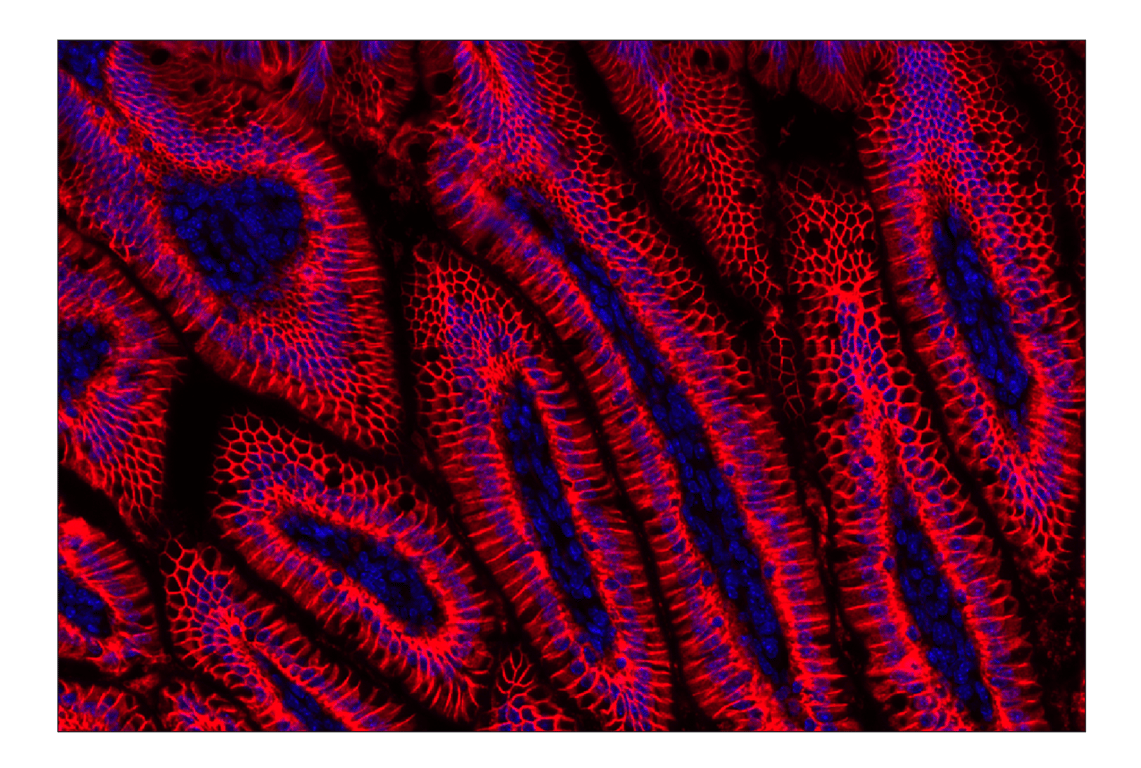

Na,K-ATPase alpha1 (F7K1P) Rabbit Monoclonal Antibody (Alexa Fluor® 647 Conjugate) #97571

Immunohistochemistry (Paraffin) 1:100 - 1:400

Na,K-ATPase alpha1 (F7K1P) Rabbit Monoclonal Antibody (Alexa Fluor® 647 Conjugate) recognizes endogenous levels of total Na,K-ATPase alpha1 protein. This antibody does not cross-react with other Na,K-ATPase alpha proteins. Species cross-reactivity for IF and IHC-P is mouse only.